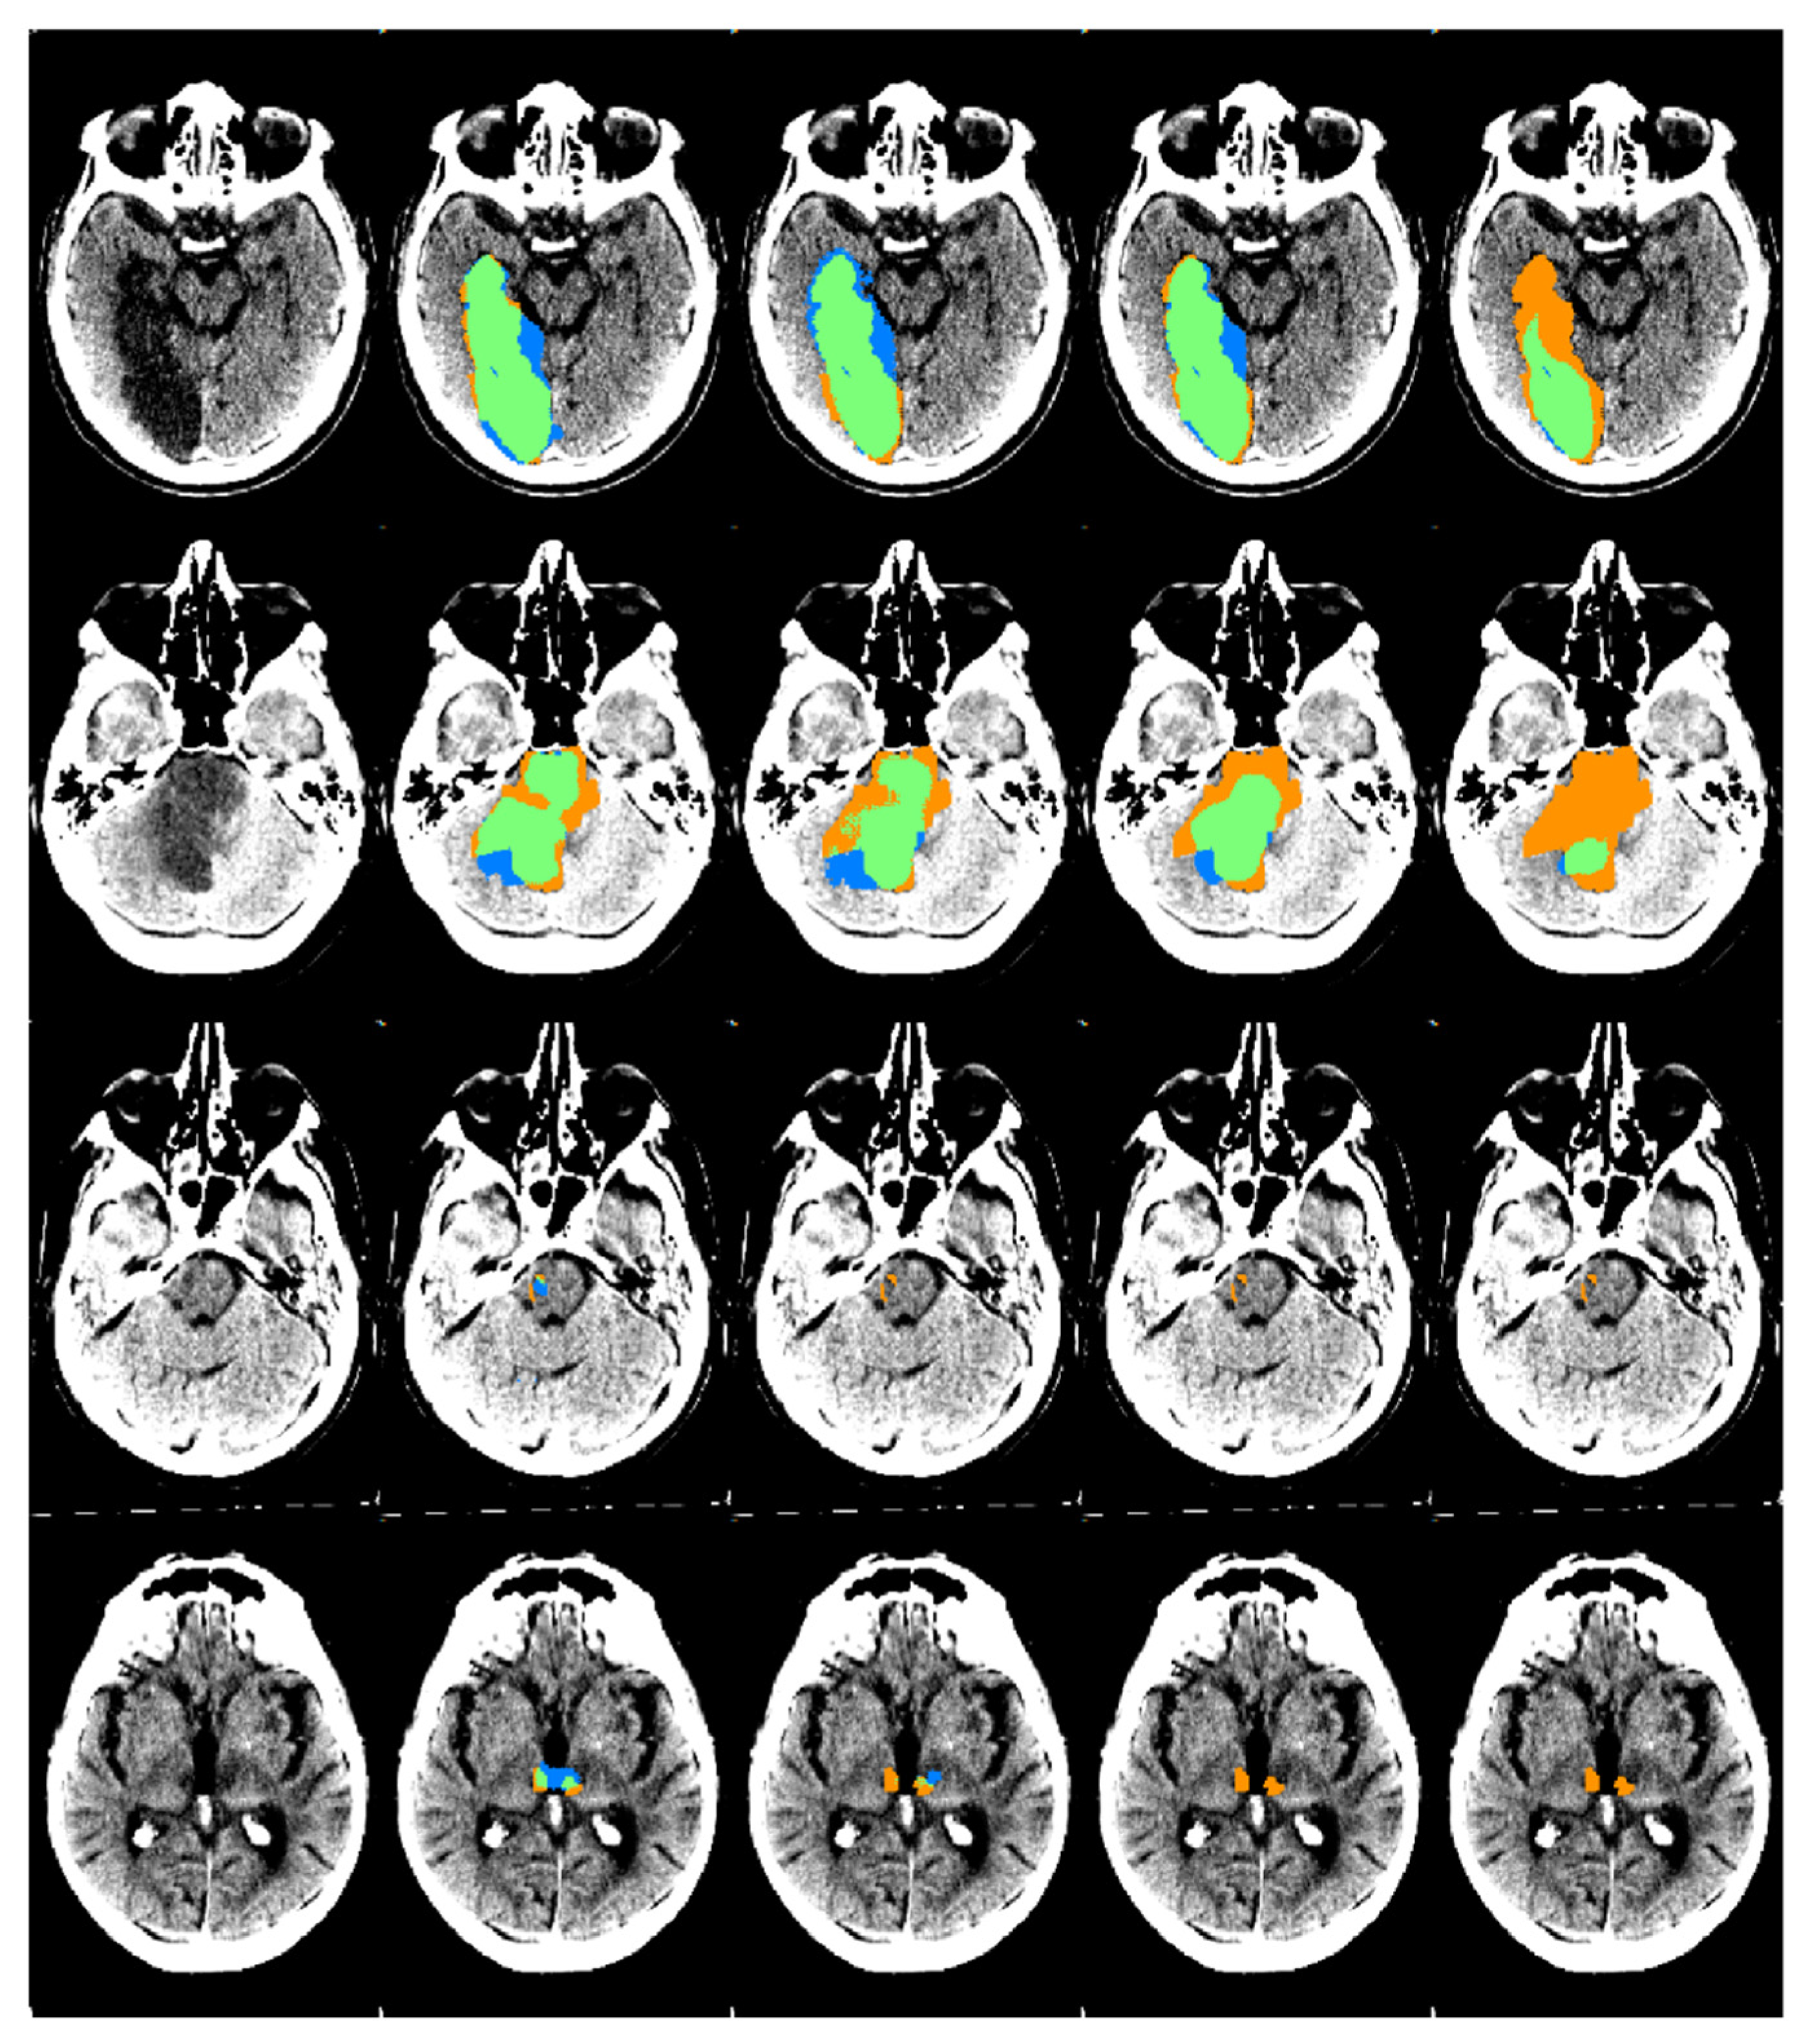

2.4. CNN for Automatic Posterior Circulation Lesion Segmentation

3. Results